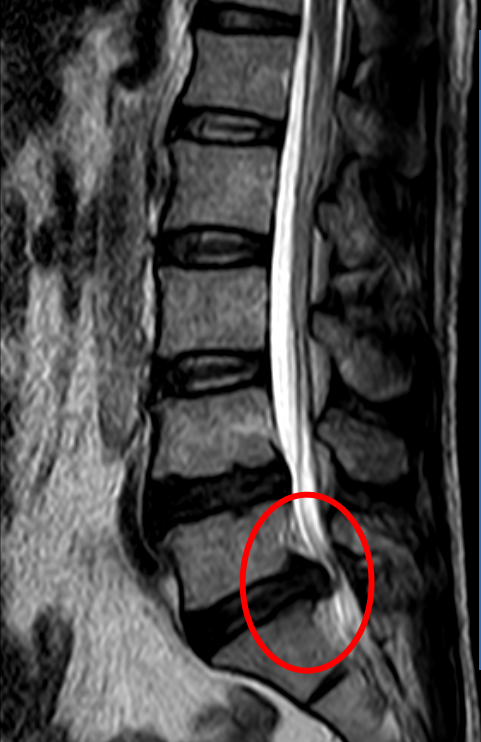

通過(guò)手術治療,周先生右側腰腿的疼痛和麻木感得到了顯著的緩解,周先生不由感慨:“整個人都(dōu)松快了!早知道(dào)應該到醫院及時(shí)及早治療,也不至于讓自己痛苦那麼(me)久了!”